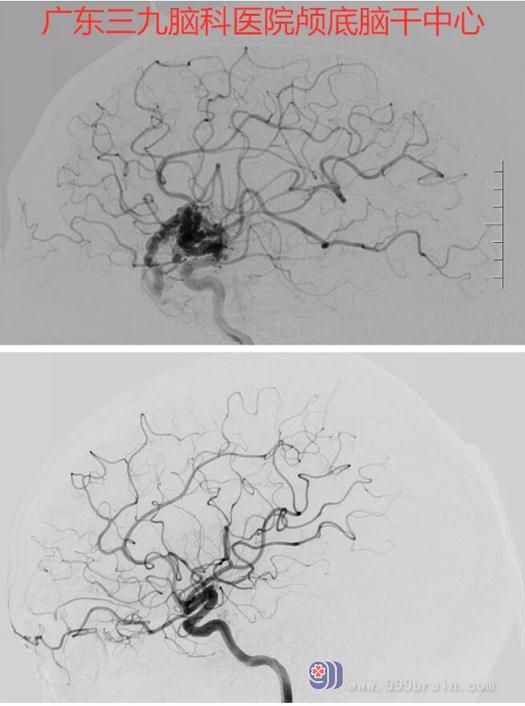

术前术后DSA对比右侧颞叶动静脉畸形术后改变,未见畸形残留。